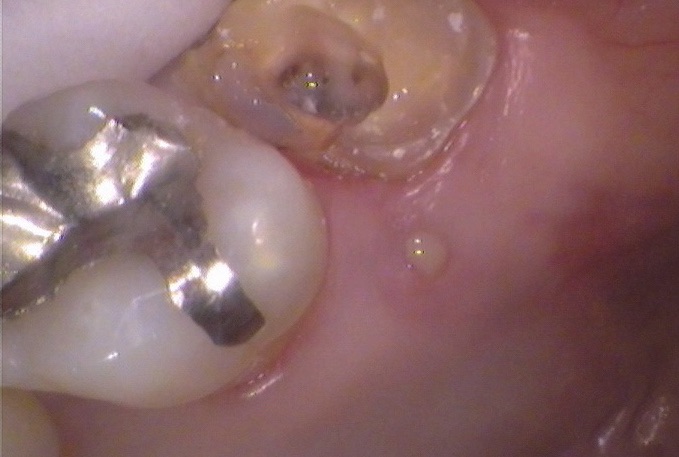

その後、数年ぶりにお越しの際、歯肉におでき(フィステル、サイナストラクト)が認められ撮影したレントゲンで根尖病変が大きくなっていたので、自覚症状はないようでしたがご説明を差し上げ、治療を開始しました。

そこで元々装着されていた金属冠を外して、根管治療を始めました。根管治療とは神経の治療と俗に言われる治療です。虫歯があればしっかり除去し、根管内をキリのような道具と洗浄液を使用して感染部分を除いて、根管充填材をつめるまでをさします。